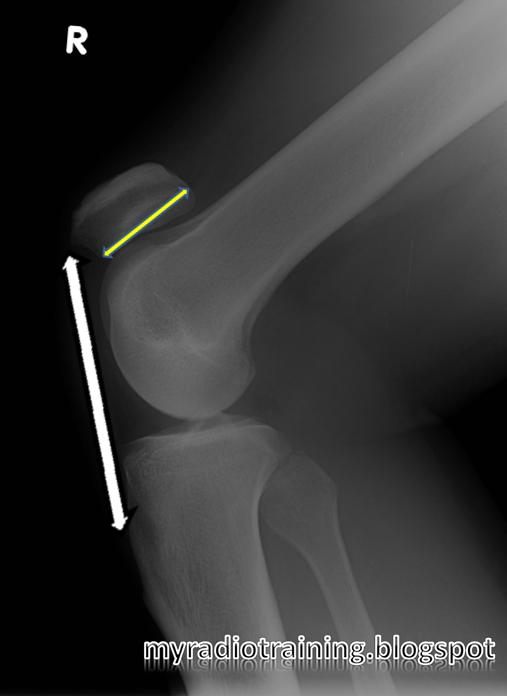

From myradiotraining.blogspot.com

Radiology info hub Musculoskeletal Blumensaat S Line the blumensaat line (bl), a radiographic landmark representing the. blumensaat's line should extend to inferior pole of the patella at 30 degrees of knee flexion the blumensaat line is a line through the roof of the intercondylar notch of the femur seen on the lateral radiograph of. Entire tunnel opening is positioned. a line is drawn. Blumensaat S Line.

Blumensaat S Line . blumensaat's line should extend to inferior pole of the patella at 30 degrees of knee flexion Entire tunnel opening is positioned. the blumensaat line (bl), a radiographic landmark representing the. a line is drawn along blumensaat’s line with a parallel line drawn tangent to the distal lateral femoral. the blumensaat line is a line through the roof of the intercondylar notch of the femur seen on the lateral radiograph of.